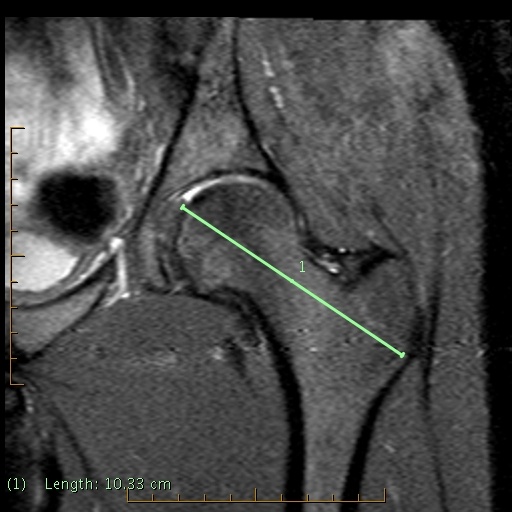

You are shown two MRI images. One is a standard orthogonal coronal with a line through it. This shows the angle of acquisition to evaluate the alpha angle. The second image is the axial oblique with the lines used for alpha angle measurement. Questions:

- The yellow line in the second image is placed from the center of the femoral head to the junction of the medial transition of the upper femoral head to the bump. The green line bisects the center of the femoral head, neck, and trochanteric region as demonstrated on the axial oblique image.

- Normal alpha angle is 55 to 60 degrees or less.

- Increased alpha angles suggest cam impingement syndrome or impingement syndrome type 1.

- Athletic, large men often have abnormal alpha angles in the absence of symptoms. Therefore, the alpha angle is not pathognomonic of symptomatic cam impingement, only suggestive.